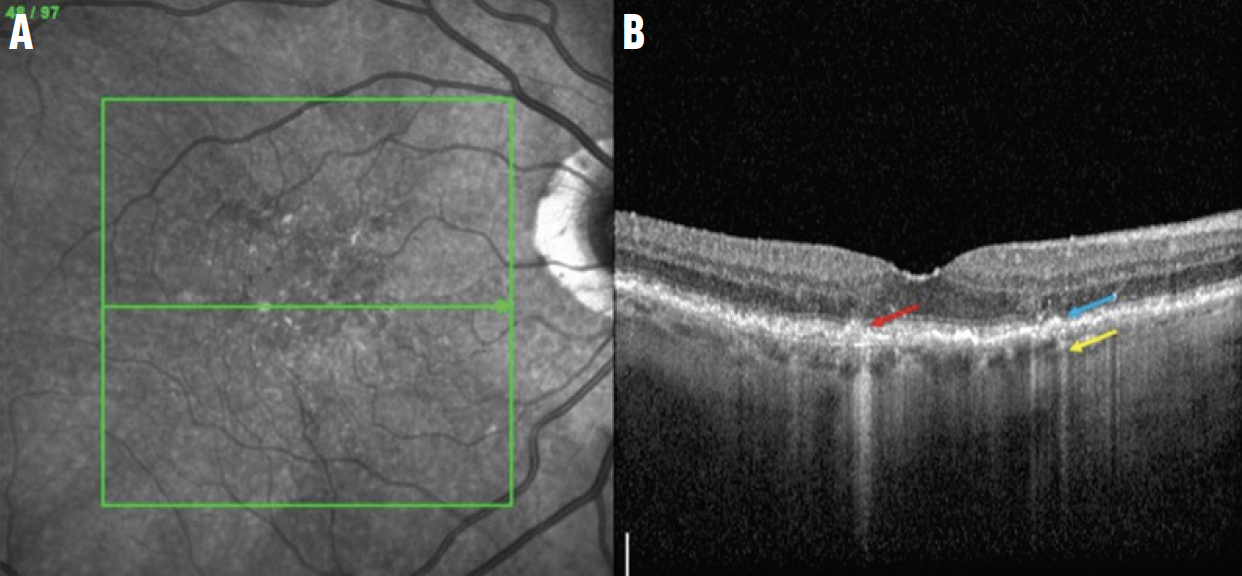

Рис. 1. Зображення в ближньому інфрачервоному діапазоні (NIR) (A) та В-скан ОКТ cRORA ураження (B) відображають порушення ELM and EZ (сині стрілки) та ділянки зменшення RPE (червоні стрілки) з гіпертрансмісією в хоріоїдею (жовті стрілки). Є ділянки дегенерації фоторецепторів (помаранчеві стрілки) і дегенеративна кіста (зелена стрілка).